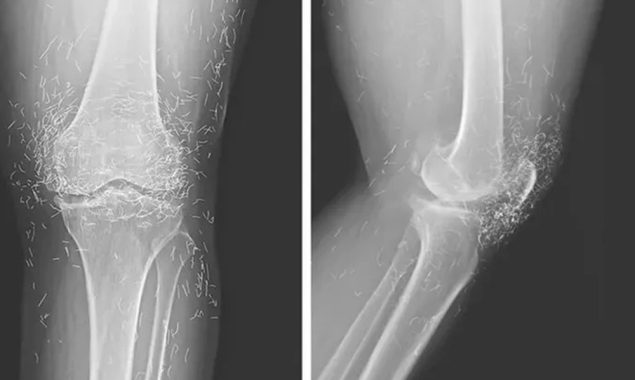

جنوبی کوریا میں ڈاکٹرز کی ٹیم اس وقت حیران رہ گئی جب انہیں گھٹنوں کے درد میں مبتلا خاتون کا ایکسرے کرنے پر سونے کے کئی دھاگے کے دکھائی دیے۔

ابتدائی طور پر وہ ہر ہفتے ایکیوپنکچر کے سیشنز لیتی تھیں، جن میں چھوٹے چھوٹے سونے کے دھاگے گھٹنوں کے اردگرد داخل کیے جاتے تھے، لیکن اس سے اُن کے درد میں اور اضافہ ہو گیا۔ لیکن انہوں نے ہفتے میں کئی بار سیشن لینا شروع کیے تاکہ انہیں آرام مل سکے۔ تاہم کچھ عرصے بعد درد اس قدر بڑھ گیا کہ انہیں دوبارہ اسپتال جانا پڑا۔